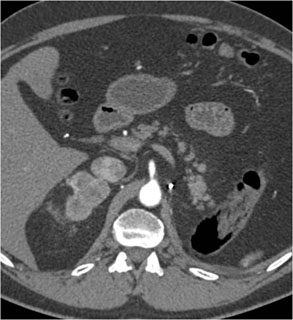

In this patient the best dx is?

adenoma

pheochromocytoma

metastatic renal cell carcinoma

cyst